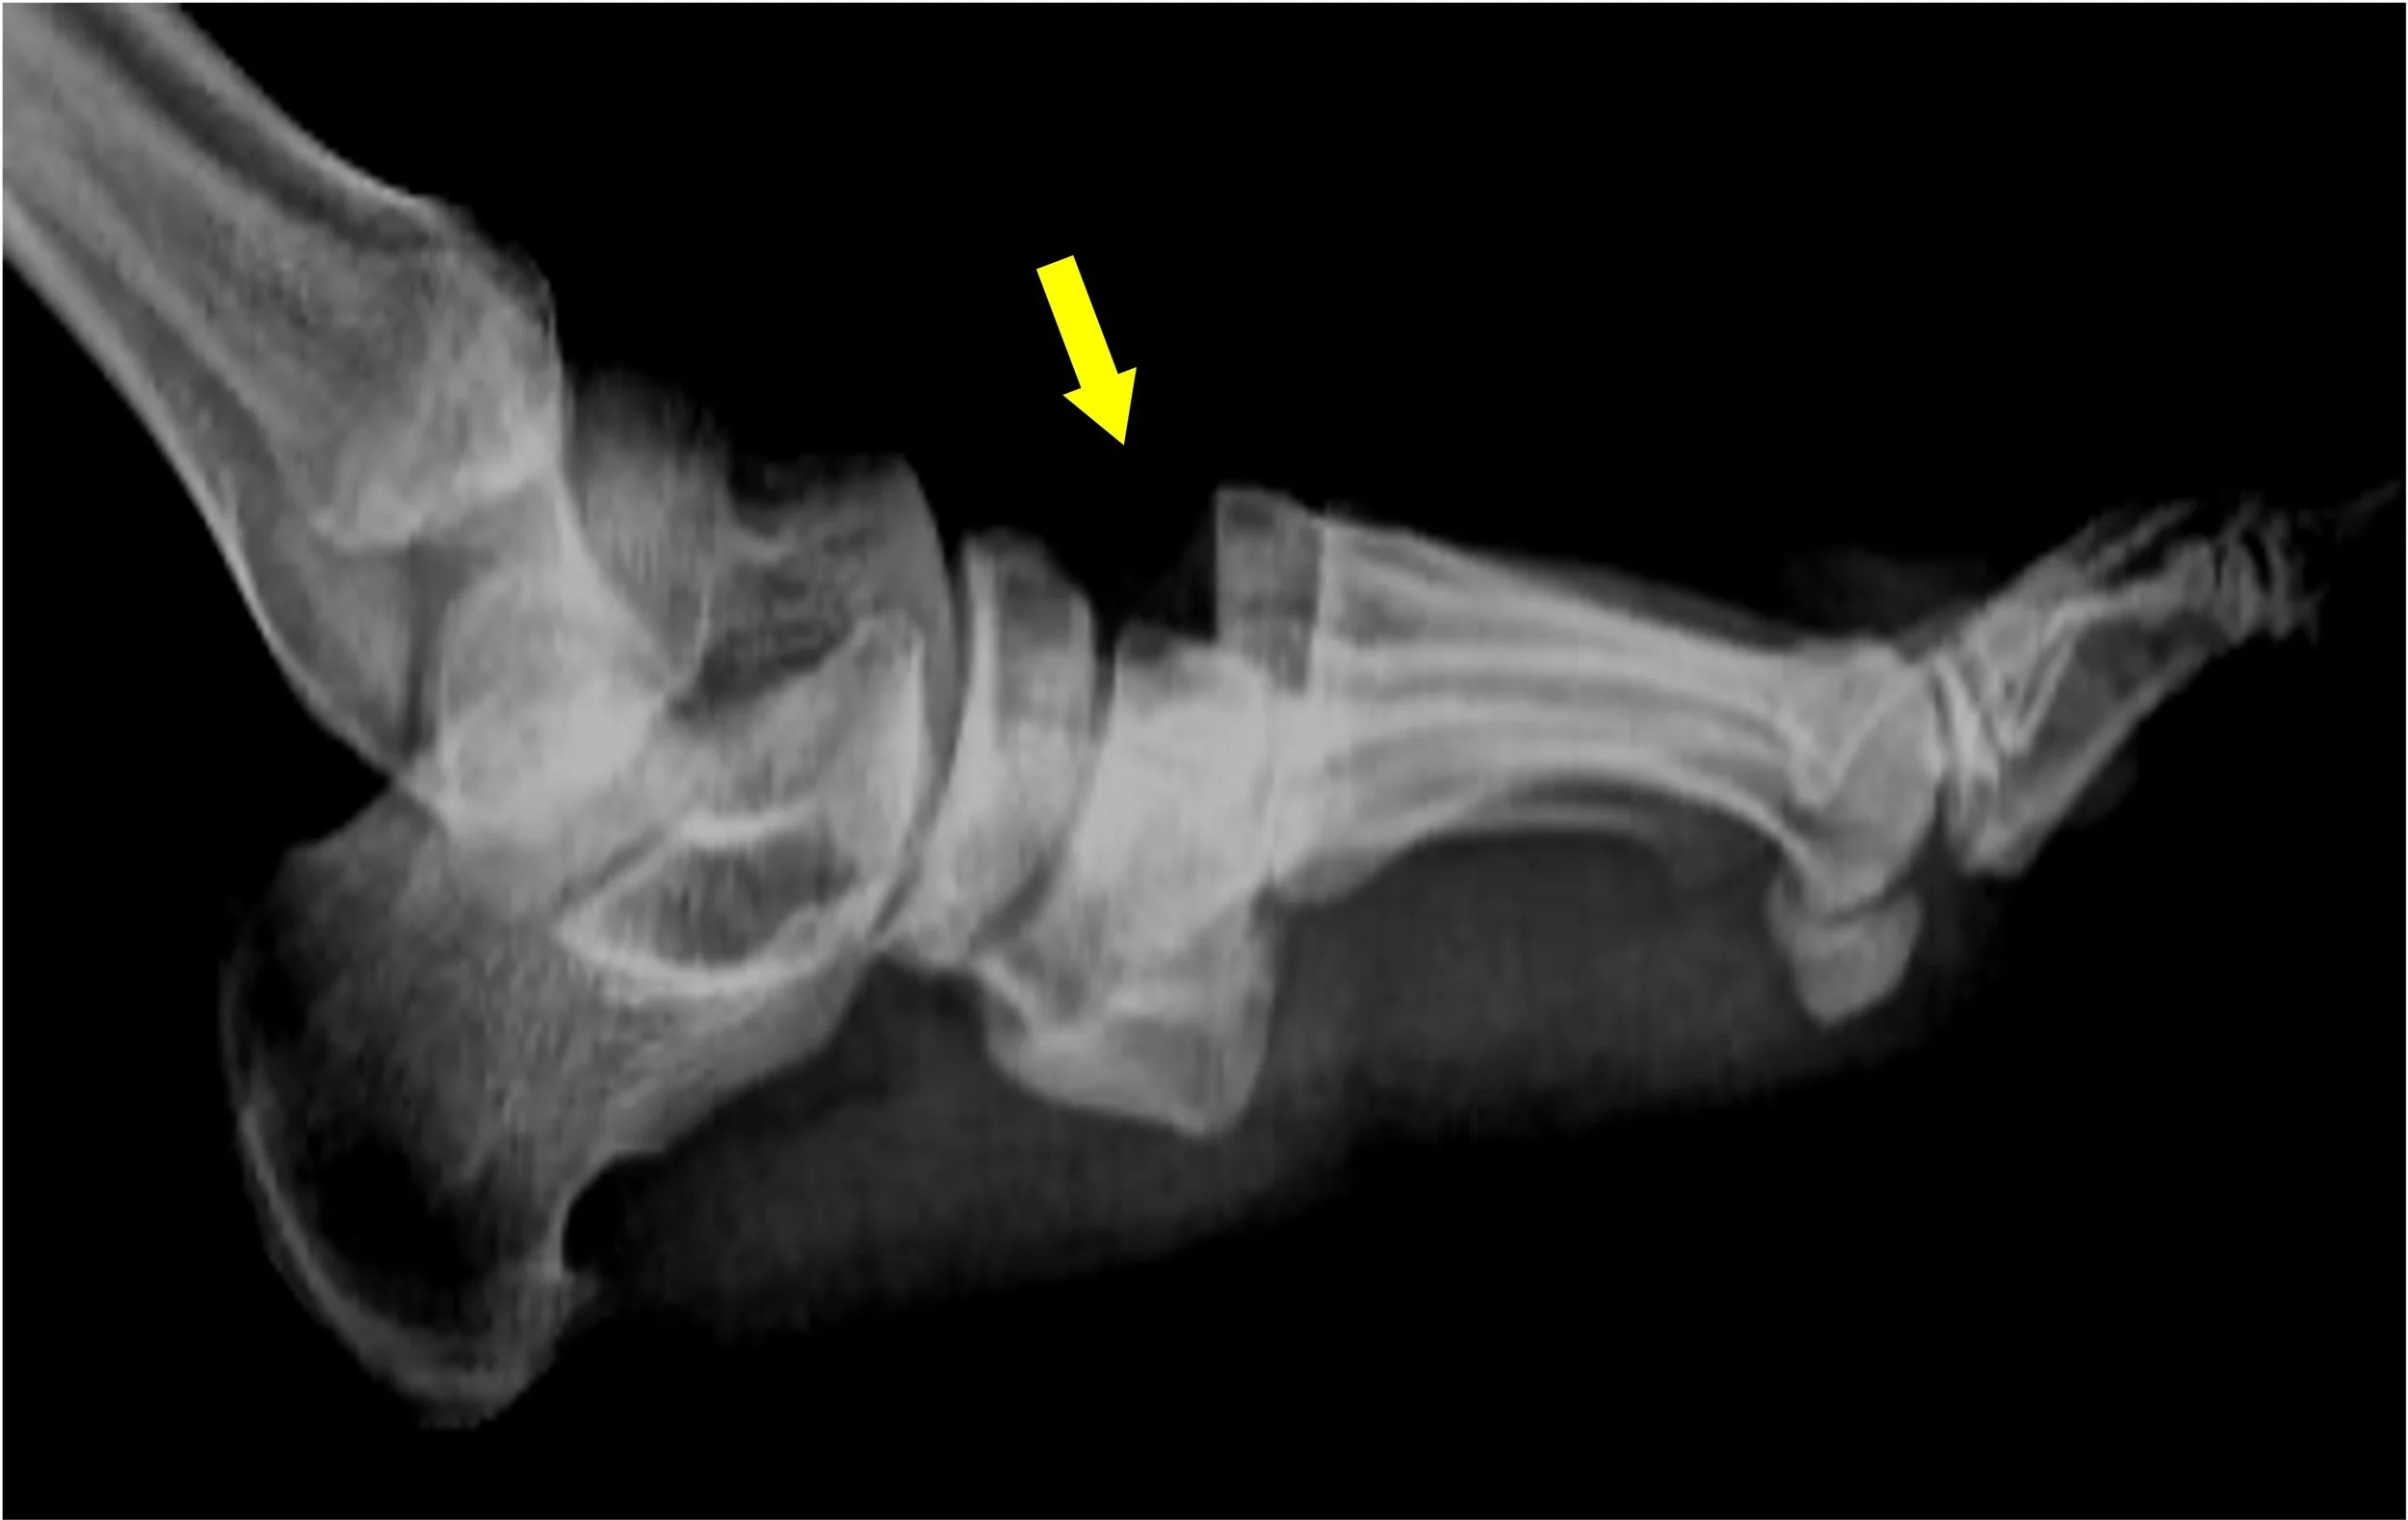

Hindfoot Fractures

• Calcaneal (Heel) Fractures: Often caused by falls from height.

• Talar Fractures: Serious injuries affecting the "plug" of the ankle joint.